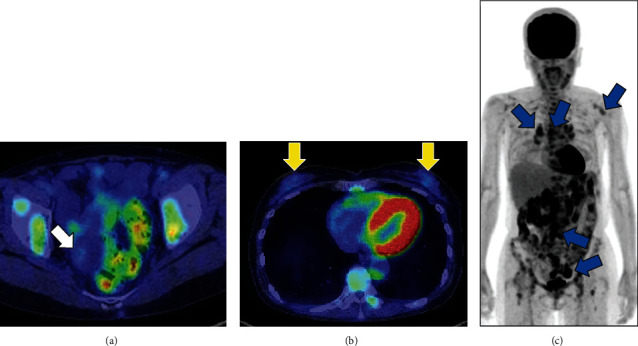

诊断性腹腔镜检查在治疗妇科癌症方面非常有用,但偶尔也会发现其他恶性肿瘤。隐匿性乳腺癌(OBC)是指没有公认的原发性乳腺病变的转移性乳腺癌。我们报告了一例罕见的通过腹腔镜发现的隐匿性乳腺癌。一名 64 岁的女性因背部疼痛来我院就诊。磁共振成像(MRI)显示右侧卵巢有一个 50 毫米的多囊性肿瘤,内部有一个结节。正电子发射断层扫描/计算机断层扫描显示多个淋巴结有异常积聚,卵巢肿瘤结节有中度积聚,乳房无积聚。怀疑是卵巢癌,于是进行了腹腔镜诊断。腹腔镜下观察到右侧卵巢有一个囊性肿瘤,右侧圆韧带有一个 10 毫米的结节,并进行了部分切除。免疫组化病理结果显示,圆韧带结节的特征与乳腺癌一致,但卵巢肿瘤是血清粘液性边界肿瘤。磁共振成像显示没有乳腺病变。因此,该恶性肿瘤被诊断为卵巢癌。

Diagnostic laparoscopy is useful in the management of gynecological cancers; however, it can occasionally result in the detection of other malignancies. Occult breast cancer (OBC) is metastatic breast cancer without a recognized primary breast lesion. We report a rare case of OBC that was detected laparoscopically. A 64-year-old female presented to our hospital with back pain. Magnetic resonance imaging (MRI) revealed a 50 mm multicystic tumor with an internal nodule in the right ovary. Positron emission tomography/computed tomography showed abnormal accumulation in multiple lymph nodes, moderate accumulation in the ovarian tumor nodule, and no accumulation in the breasts. Ovarian cancer was suspected, and a diagnostic laparoscopy was performed. Laparoscopically, a cystic tumor in the right ovary and 10 mm nodule in the right round ligament were observed and partially resected. Immunohistopathologically, the nodules of the round ligament exhibited features consistent with those of breast cancer, but the ovarian tumor was a seromucinous borderline tumor. MRI revealed no breast lesions. Therefore, the malignancy was diagnosed as an OBC.